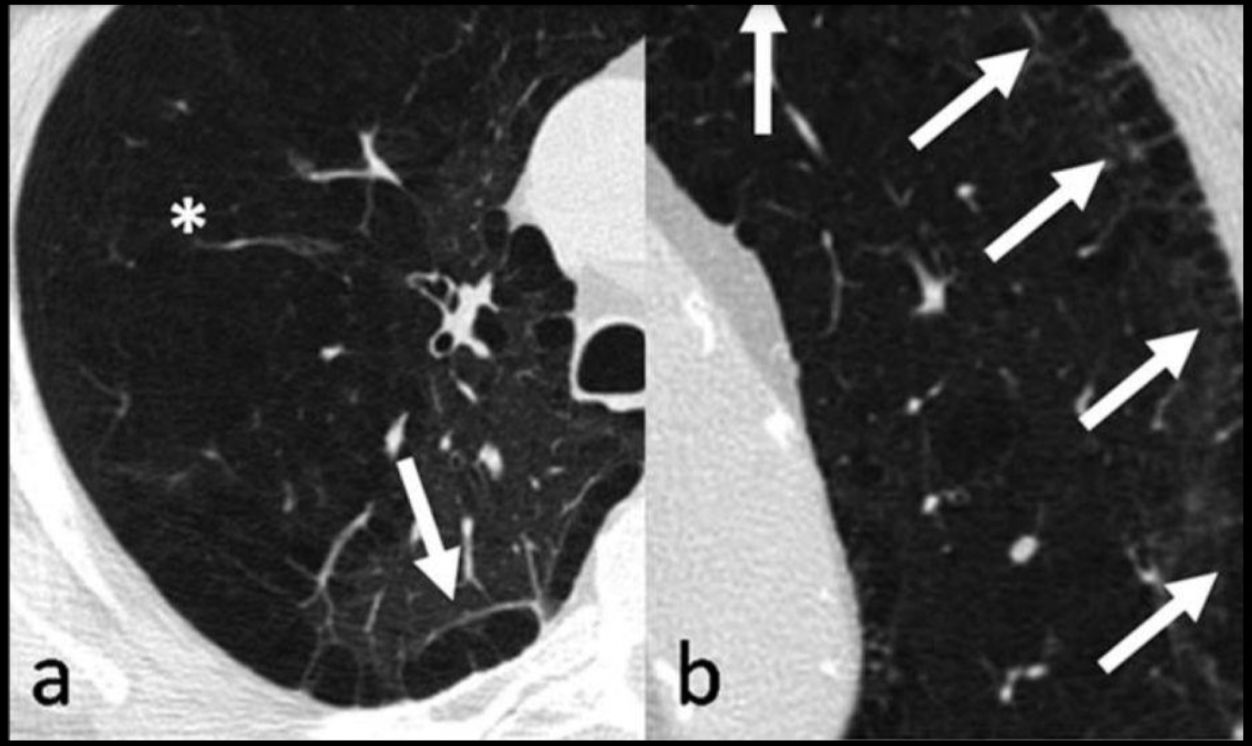

13

Q

¿Qué patrón es, qué signo es y de qué enfermedad es?

A

• Bronquiectasia

• Rieles de tren

• Bronquitis crónica

14

¿Qué signo es y que enfermedad lo tiene?

Manguito peribronquial

Bronquitis crónica

15

¿Qué signos encuentras que te indican de una bronquitis crónica?